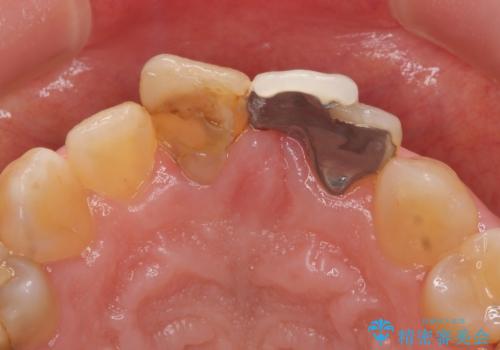

- 前歯の歯並びや色が気になるといらっしゃった方の症例です。

前歯4本をオールセラミッククラウンで補綴することで、歯の並びや色の改善を行いました。

- オールセラミッククラウン…¥100,000×4、仮歯…¥10,000×4費用は治療当時の料金となります

今回用いたオールセラミッククラウンはジルコニアフレームという白い素材の上にセラミックを盛っているため、審美性が非常に高いのが特徴です。